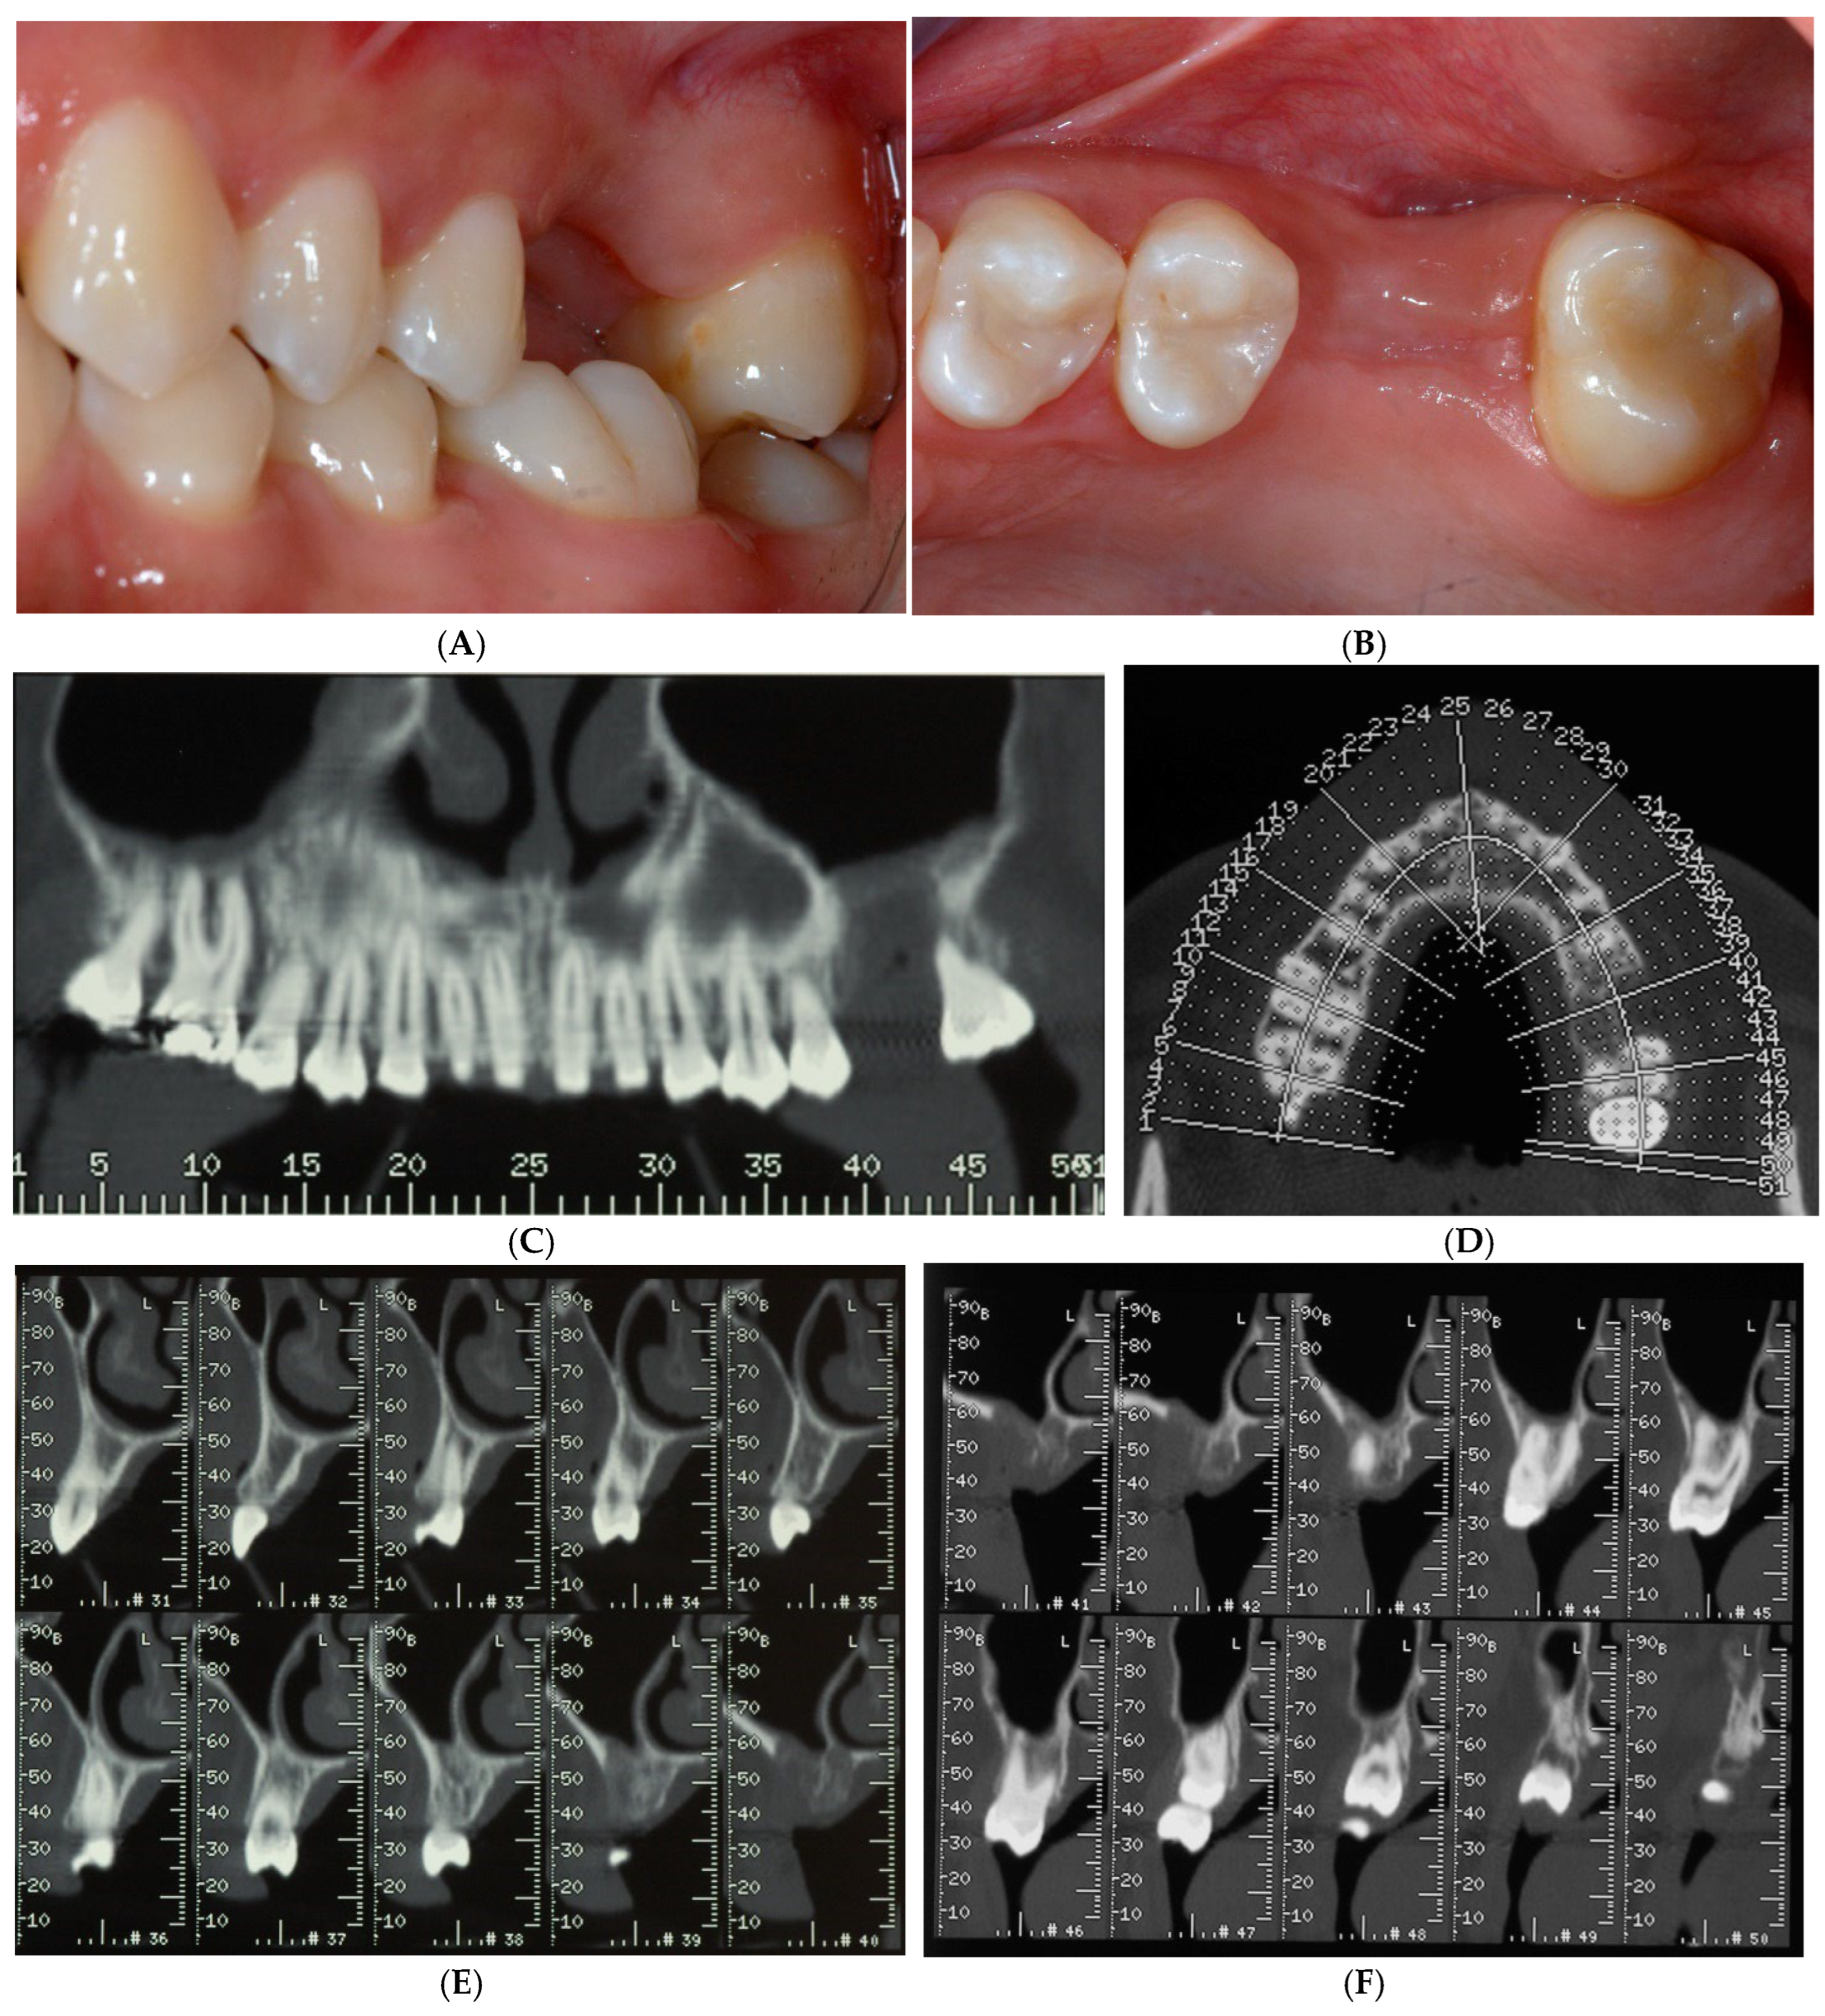

After making the crestal incision, two vertical buccal releasing incisions—mesial to the second premolar and distal to the second molar—were performed. Then, a mucoperiosteal flap was raised, revealing the wide ridge deficiency (approximately 5, 7, and 9 mm in the mesio-distal, bucco-palatal, and corono-apical directions, respectively), highlighting the impossibility of achieving proper implant stability (Figure 3A,B). Then, a copious bleeding recipient site was created by bur perforations through the medullary spaces. A TR-dPTFE membrane (Cytoplast® Ti 250 Buccal, Osteogenics Biomedical, Lubbock, TX, USA) was shaped and trimmed with scissors to fit the ridge defect (Figure 4A), taking care to position the membrane edges 1.5 mm away from the adjacent roots, and stabilized with two pins on the buccal side. A graft of 100% NH embedded in a silica gel matrix (NanoBone® Artoss, Rostock, Germany), in the form of 0.6 × 2 mm granules, wetted with sterile saline (Figure 4B), was applied and compacted with a spoon/plugger tool to avoid leaving voids, but without over-compacting the material (Figure 4C). The membrane was moved to the palatal side and stabilized with an additional pin to the palatal bone wall (Figure 4D,E). A continuous periosteal incision along the entire length allowed the buccal flap to move coronally, followed by tension-free suturing using horizontal mattress and single stitches (Figure 5A) with PTFE material (Cytoplast® suture, Osteogenics Biomedical, Lubbock, TX, USA), which were removed 14 days later (Figure 5B). Healing was uneventful, and after a period of 10 months (Figure 6A–C), the site was re-opened for membrane removal and implant insertion. A smaller paramarginal trapezoidal mucoperiosteal flap, sparing the periodontum of the adjacent teeth, was raised (Figure 6D,E). The membrane was easily removed, and the defect appeared to be completely regenerated (Figure 6F). A 4 mm wide trephine bur (Stoma®, Emmingen-Liptingen, Germany) was used to harvest a bone biopsy (Figure 7A), measuring 3 mm in diameter and about 6 mm in length (Figure 7B), so as not to extend the future implant bed preparation. The implant bed was then definitively prepared with the drill dedicated to the chosen implant (Figure 7C), a 5.0 × 9 mm implant (Camlog® Screw Line Promote Plus Biotechnologies, Basel, Suisse). The bone biopsy was immediately fixed in 10% neutral buffered formalin and stored at room temperature. The specimen was then decalcified in formic acid, dehydrated in progressively more concentrated ethanol, and finally embedded in paraffin. Sections of 5–6 µm thickness were cut with a microtome (Leica SM 2.400, Solms, Germany) and stained with hematoxylin and eosin and the Azan–Mallory staining technique for light microscopy. Histological evaluation and photo documentation were performed using the Axiophot microscope (Zeiss, Göttingen, Germany) at 12.5×, 25×, 100×, 200×, 400× magnifications.

Figure 6.

Radiographic (A) and clinical (B,C) follow-up after a 10-month healing period. Site was re-opened for membrane removal and implant insertion. Smaller paramarginal trapezoidal mucoperiosteal flap, sparing the periodontum of adjacent teeth, was raised (D,E). Membrane was easily removed, and defect appeared completely regenerated (F).

Figure 7.

Trephine bur was used to harvest bone biopsy (A), measuring 3 mm in diameter and about 6 mm in length (B), during implant bed preparation (C). After implant insertion (D), a healing abutment was immediately connected (E) for transmucosal healing, avoiding additional surgery. Healing was uneventful and 2 months later (F), site was ready for prosthetic rehabilitation.

After implant insertion (Figure 7D), a healing abutment was immediately connected (Figure 7E) for transmucosal healing, avoiding additional surgery. After a 2-month healing time (Figure 7F), a provisional restoration was applied for progressive loading. At 6 months after implant insertion, a definitive porcelain-fused-to-metal crown was cemented (Figure 8A–C).